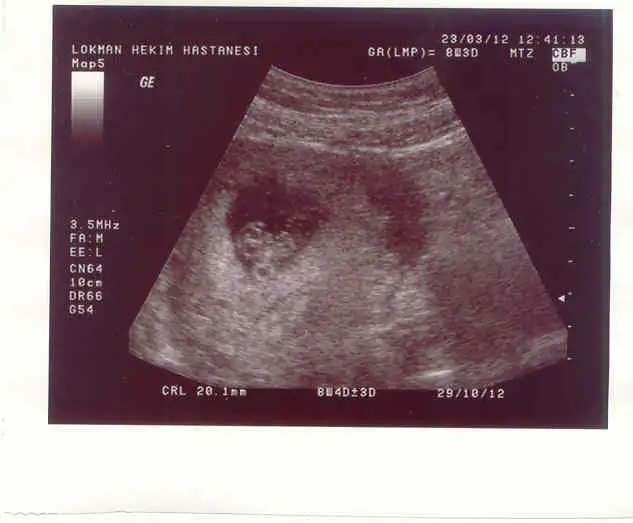

bebişlerimizi tam görüyorken tadını çıkaralım bence..

doğru söylüyon canımmm. ama çokkk zevkli ultrasonda izlemek yaaaaaaaaaaaa

maşallahhh cnmm öpsünler minişiniiii

41 kere Maşallah